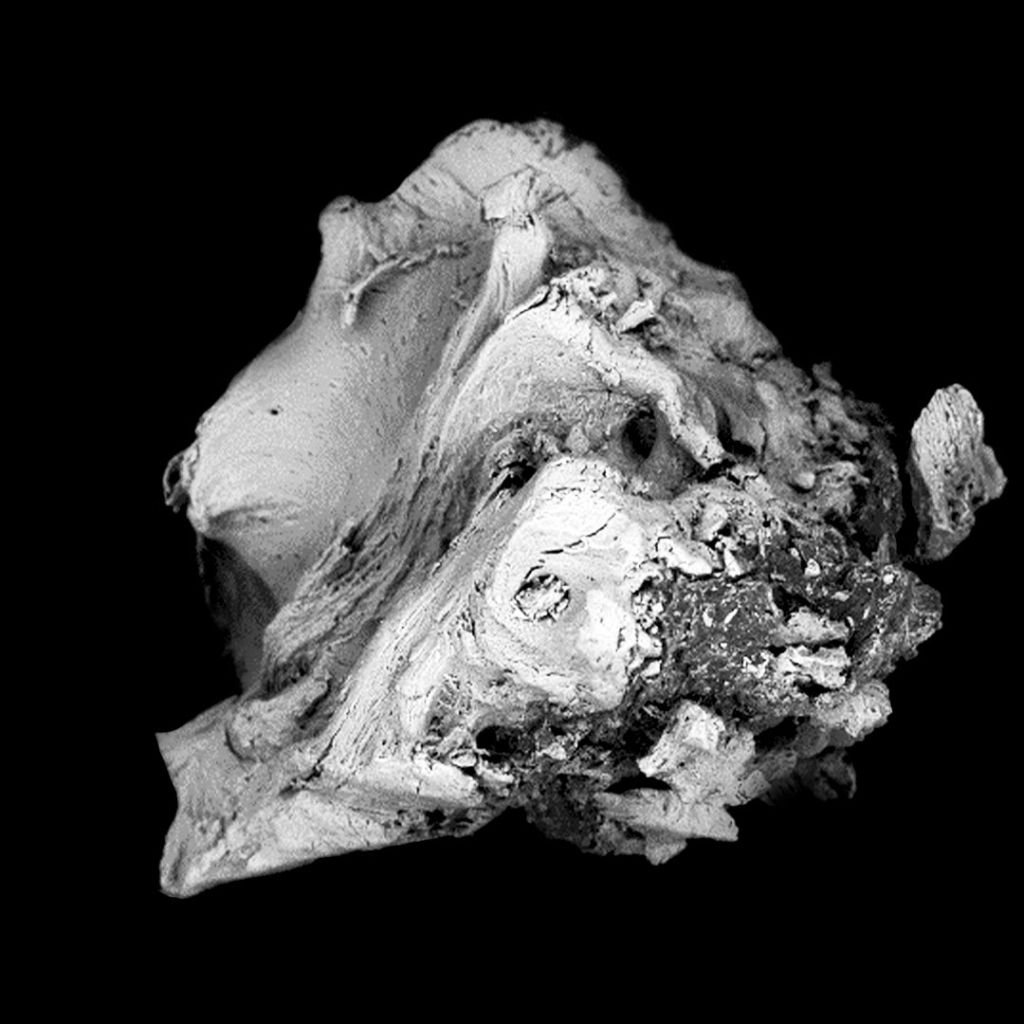

Análisis topográfico.

La microestructura del injerto óseo Bonefill® , analizada mediante SEM/EDS, reveló que el producto presenta una estructura típica del hueso cortical y esponjoso humano, con poros interconectados, y que, tras el proceso fisicoquímico al que se somete la materia prima para su fabricación, conserva la estructura característica de este tipo de tejido. La presencia de poros y el mantenimiento de la estructura cristalina trabecular del hueso son factores fundamentales para el éxito de los fenómenos celulares de deposición de células osteoprogenitoras sobre el injerto, su reabsorción y la formación de nuevo hueso en su lugar.